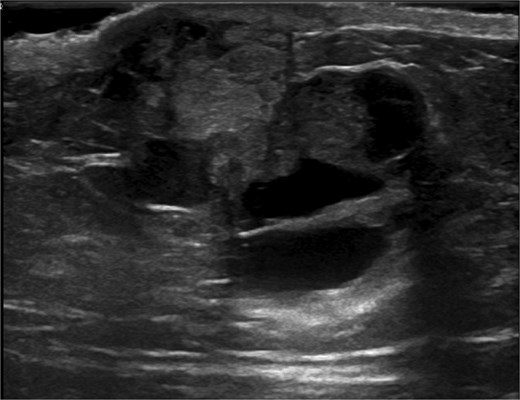

Ultrasound-guided core needle biopsy of the mass showed dissociated fragments of cribriform-like and papillary-like carcinoma (Figs 3 and 4).

Ultrasound of retroareolar area of palpable concern – first view.

Ultrasound of retroareolar area of palpable concern – second view.